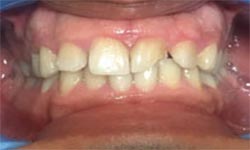

(3)Dental Veneers

Before Treatment

After Treatment

Patient with a complaint of rotated upper left lateral incisors. Veneers placed for the treatment of the rotated upper left lateral incisors.